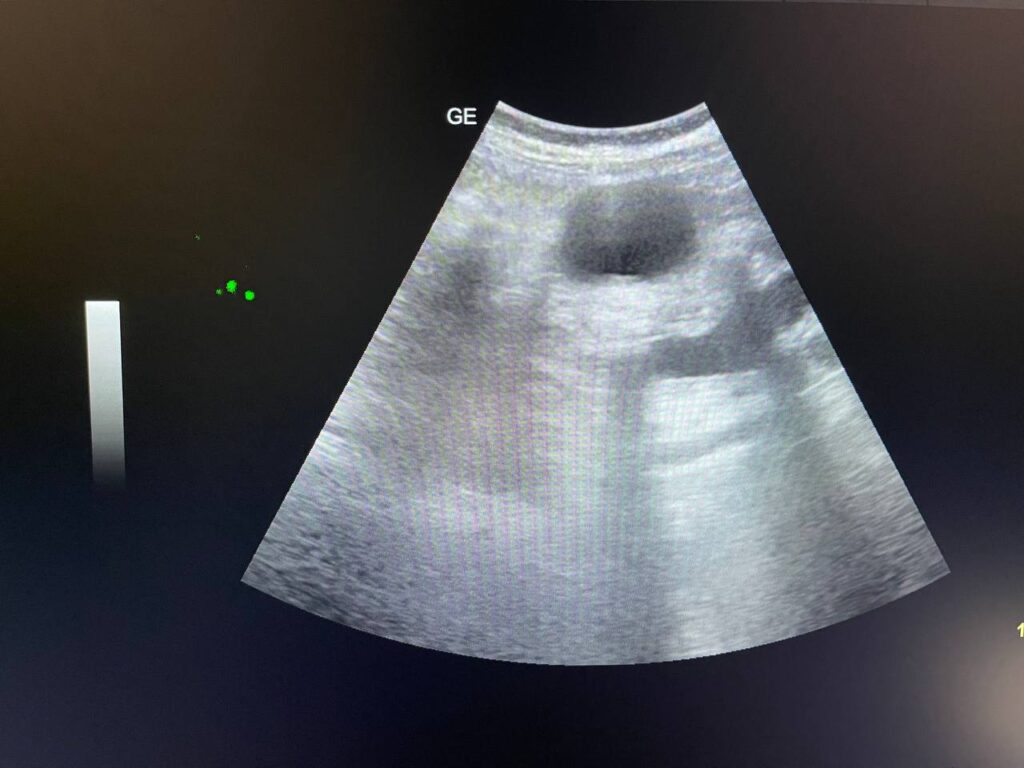

GB STONES & CBD STONE

Gall bladder distended,  increase wall thickness 5.5mm edematous, contain multiple mobile stones of variable sizes , the largest 12mm + dilated common bile duct 13mm , due to presence of stone about 25mm in the distal part